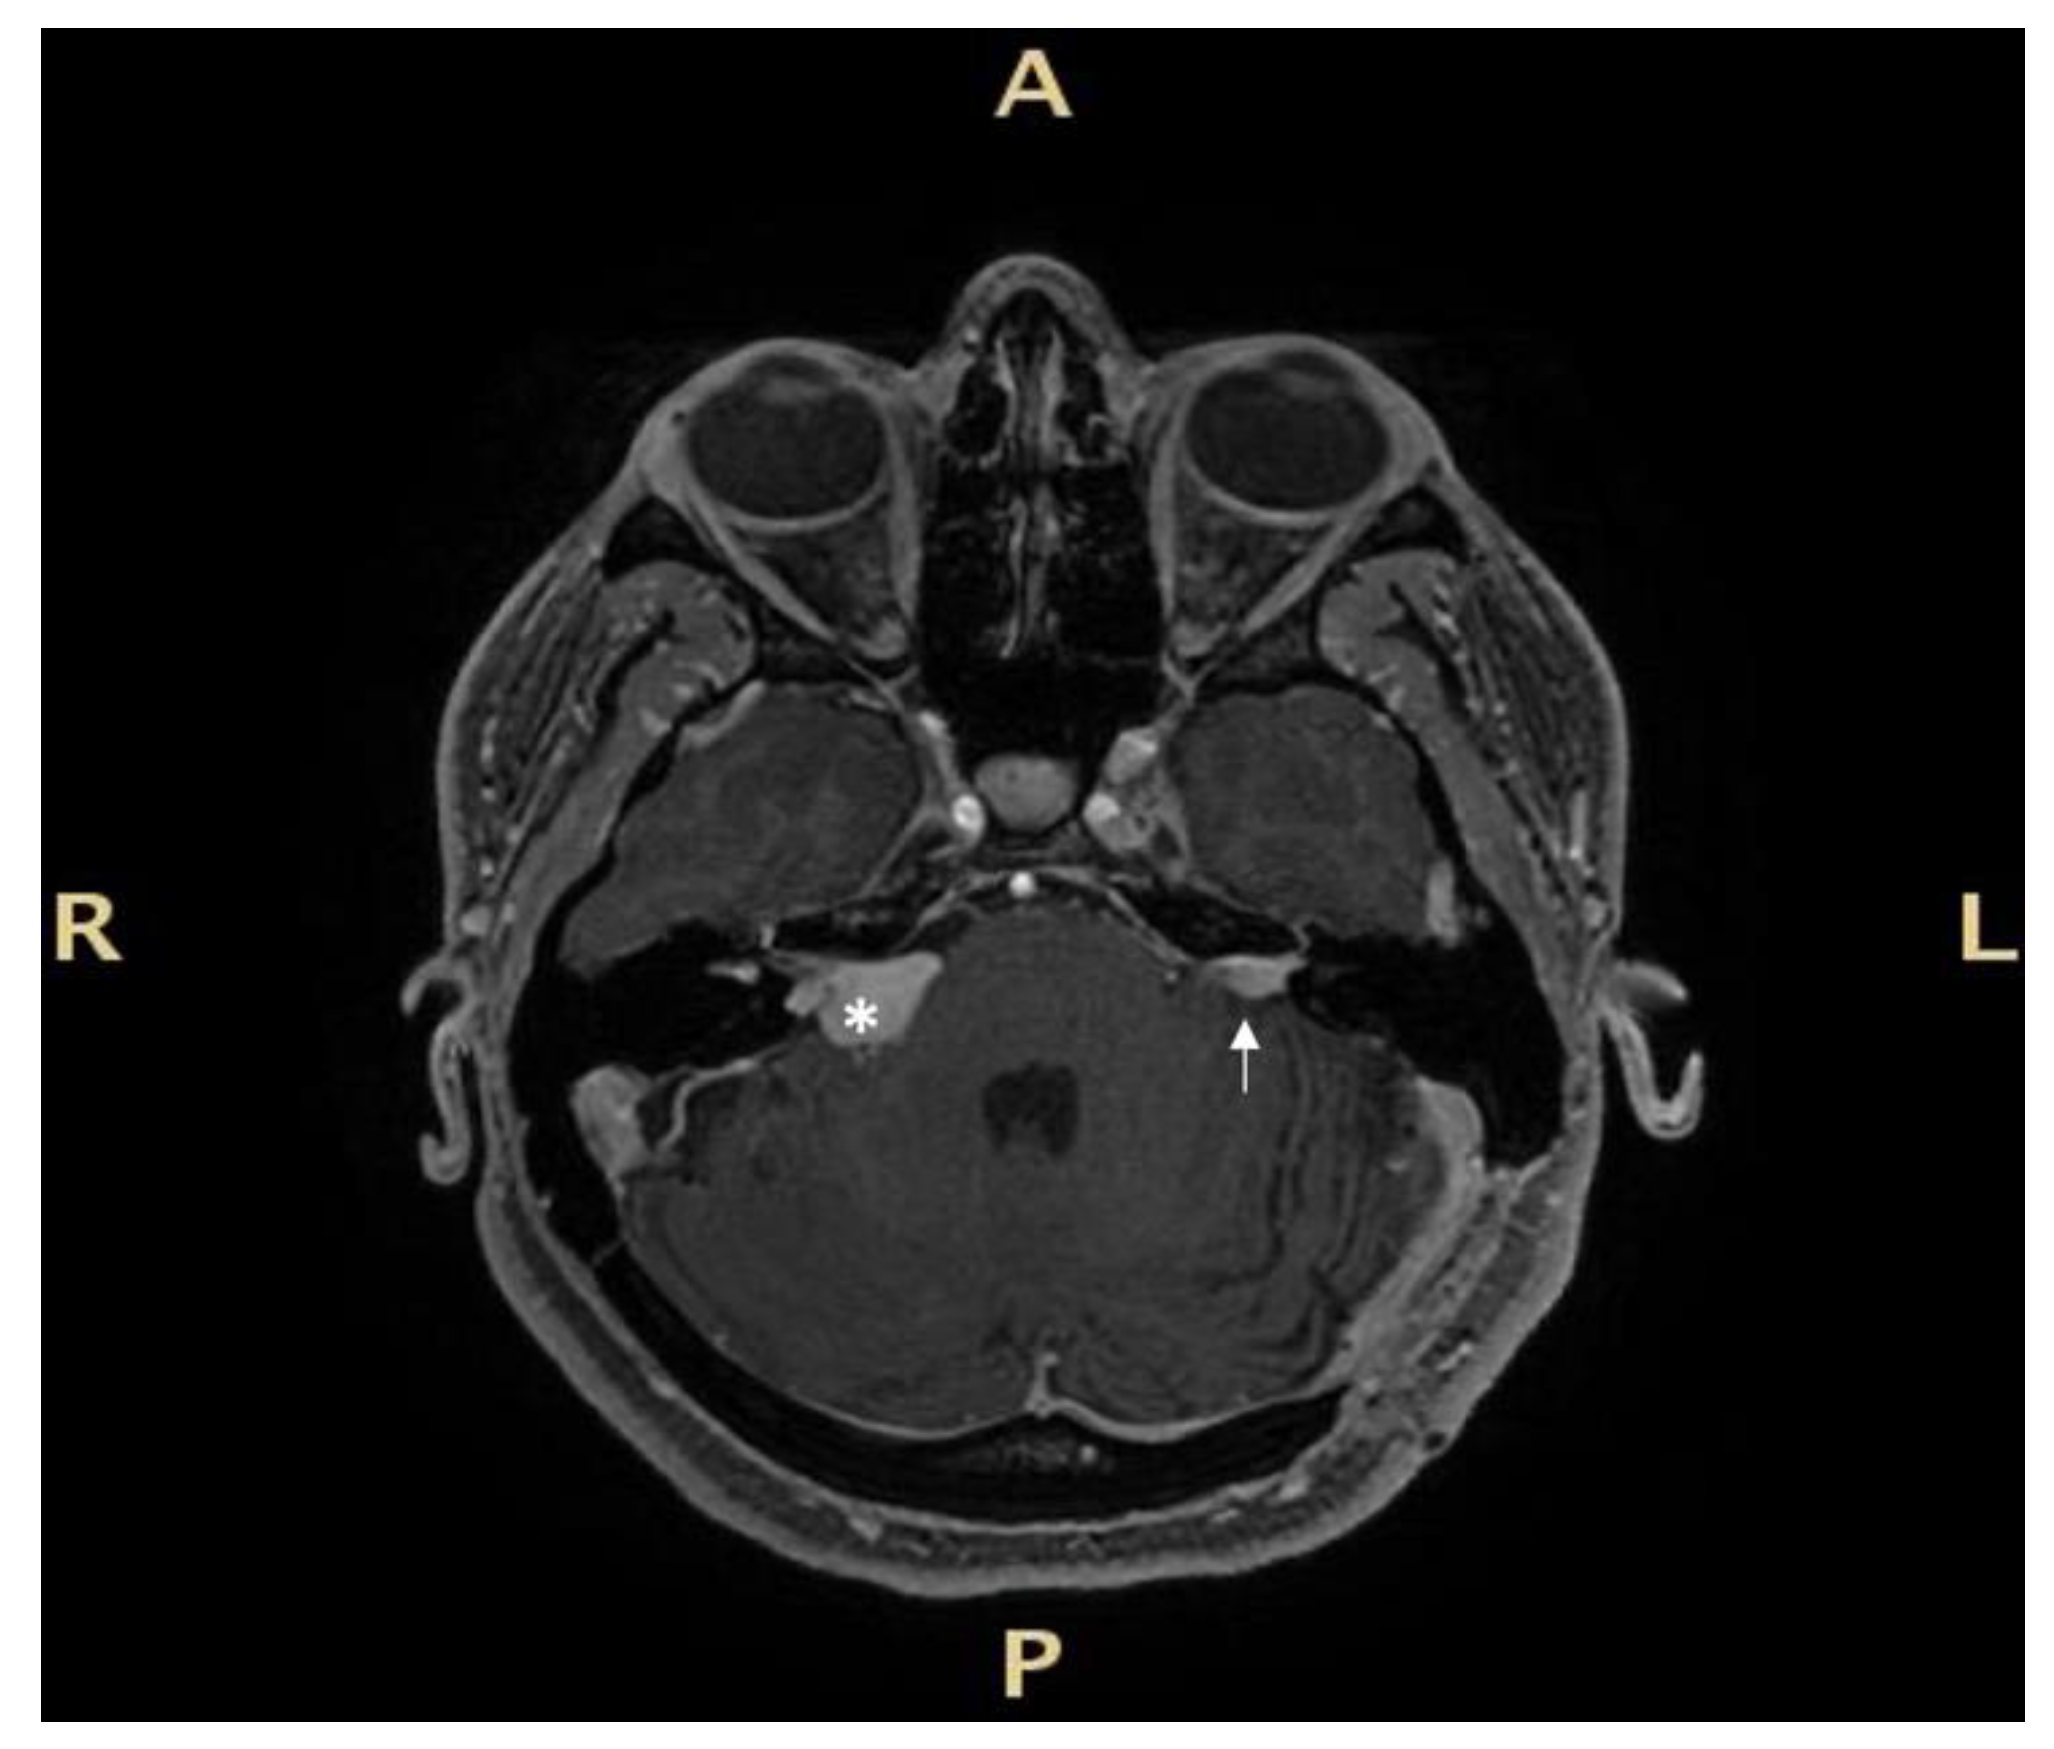

The first case involves a 33-year-old female patient with NF2 (Figure 2).

In 2009, the patient underwent stereotactic radiotherapy for right eight cranial nerve schwannoma. In 2014, the patient underwent successful hearing preservation surgery via retrosigmoid approach for a left eight cranial nerve schwannoma. Hearing was preserved in the right ear for the first six years, but after 2017, it progressively diminished, ending in deafness in 2019. While right hearing was diminishing, a tumour recurrence occurred in the left side (Figure 2). Post-radiation right ear anacusis occurred, despite tumour stability, and an homolateral intracochlear mass was evidenced, while left hearing was progressively compromised due to the recurrence, as shown in Figure 3. Before treating the left only-hearing ear recurrence (where residual and not serviceable hearing was present) in 2020, she was offered the possibility of intracochlear tumour removal and cochlear implant (CI) placement.

Figure 2. Magnetic resonance Imaging (MRI) before right cochlear implantation: right irradiated and stable tumour with intralabyrinthine component (white asterisk), and left side intrameatal recurrence (white arrow) after surgery via a retrosigmoid approach. R: right, L: left, A: anterior, P: posterior.